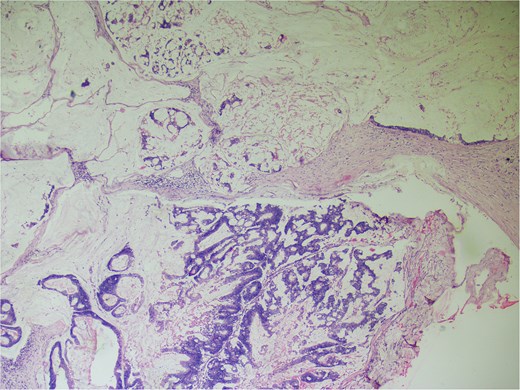

On gross examination, growth seen involving ileocecal junction extending upto caecum measuring 6.5 × 6.0 × 4.3 cm. Cut section showed solid creams white firm to friable areas with mucoid consistency at places. A nodular growth is identified in the attached mesentery measuring 3.5 × 2 × 2 cm. On cut section solid white areas are seen along with focal area showing mucoid consistency. The histopathological report concluded mucinous adenocarcinoma of caecum, pT3N1MX, with evidence of lymphovascular invasion. The tumor invaded through the muscular propria layer (Figs 4 and 5). Additionally, acute appendicitis was found.

Hemotoxylin and eosin ×100: Section shows atypical cells floating in lates of extra cellular mucin.